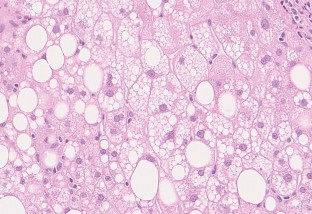

Nonalcoholic fatty liver disease (NAFLD) is based on the concept of pathological morphology as well as clinical findings, and is broadly categorized into nonalcoholic fatty liver (NAFL) and nonalcoholic steatohepatitis (NASH). The differential diagnosis between NAFL and NASH is important because NASH has the potential to progress to cirrhosis and hepatocellular carcinoma. NAFL is simple hepatic steatosis without hepatocellular injury, while NASH is characterized by macrovesicular steatosis, inflammation, and ballooning hepatocytes with a predominantly centrilobular (zone 3) distribution. Liver biopsy is a useful test for diagnosing NAFLD, but it is invasive. Therefore, various noninvasive methods including diagnostic imaging have been developed in recent years. To verify their usefulness, it is necessary to clarify in detail how the pathological findings are reflected in the image findings as imaging and histopathological findings are closely related. We describe the main histological features of NAFLD, i.e., steatosis, inflammation, ballooning hepatocytes, Mallory-Denk bodies, and fibrosis, as well as the evolutional process to liver cirrhosis.

Fig. 1